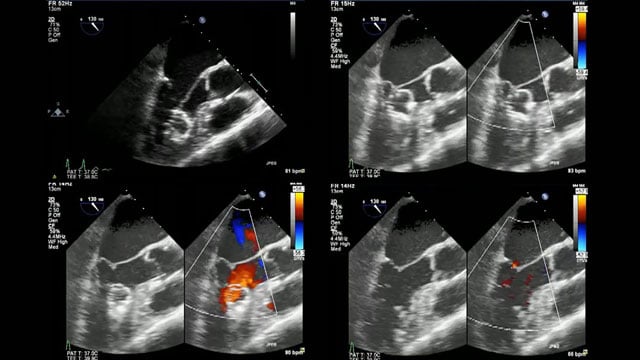

Advancing structural heart with 3D ICE and device guidance

17 Nov 2025 – From PCR London Valves 2025

This PCR London Valves 2025 session explores how 3D TEE, 3D intracardiac echocardiography (ICE), and DeviceGuide technology sharpen procedural accuracy, strengthen operator confidence, and streamline decision-making in real time.

You’ll see how clearly defined team roles enhance both safety and efficiency, and how thoughtful workflow integration can reduce...

Procedural imaging for tricuspid valve interventions

16 Nov 2025 – From PCR London Valves 2025

Master procedural imaging techniques essential for tricuspid valve interventions, including TOE views, multi-phase reconstruction, and 3D/4D steering. This session also covers quantification of residual tricuspid regurgitation post-device deployment and the appropriate use of intracardiac echocardiography.